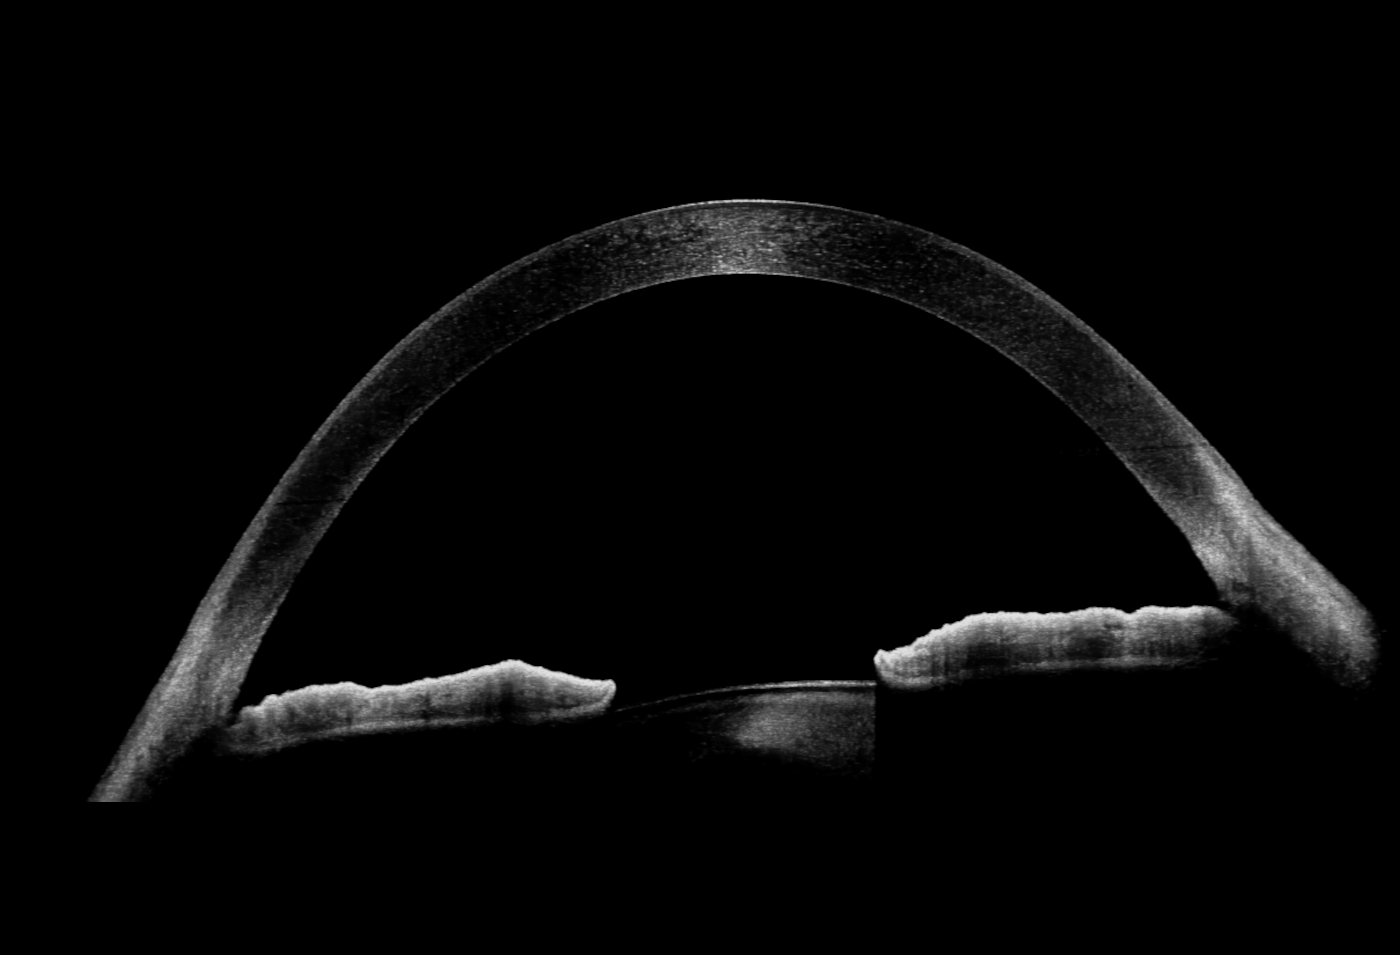

Full Range Aufnahmen

Das neue Extended Depth Retina Imaging, welches auf der Full Range-Technologie basiert, bietet Scans mit größerer Tiefe für eine zuverlässige und bequeme Kontrolle von schwierigen Fällen. Dank der Scans mit großer Tiefe ist dieser neue Bildgebungsmodus perfekt für die Diagnose von sehr stark kurzsichtigen Patienten geeignet. Außerdem bietet sie einen Überblick über die gesamte Vorderkammer, von Hornhaut bis zur Augenlinse.

- 18 mm Scan-Breite

- Darstellung des vollständigen vorderen Systems

- Messung beider Kammerwinkel in einer Aufnahme

- Automatische Pachymetrie

- Analyse des Kammerwinkels

- Darstellung der Iris